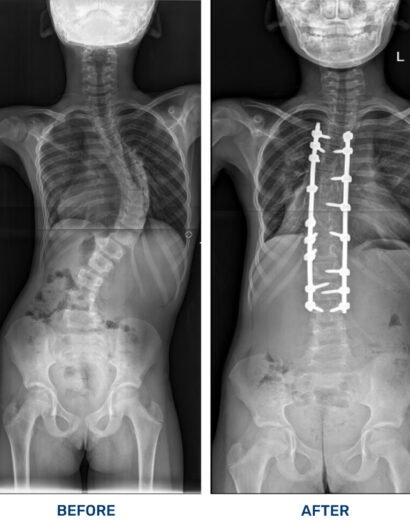

Success Stories

As Ghana’s leading orthopaedic and spine care hospital, we specialize in world-class treatments, cutting-edge surgeries, and personalized rehabilitation to help you move pain-free. Experience top-tier medical expertise, advanced diagnostic services, and patient-centered care in a state-of-the-art facility. Your health, our commitment.

FOCOS mission is to provide comprehensive, affordable orthopaedic care to those who would not otherwise have access to such treatment. Specifically, we strive to improve accessibility to top-notch surgical and non-surgical care for patients who suffer from debilitating musculoskeletal conditions, such as complex spine deformities and pediatric orthopedic problems, in underserved areas. It all began as a dream of the founder to see the best care reach the underserved in his native country, Ghana and the sub-Saharan region.